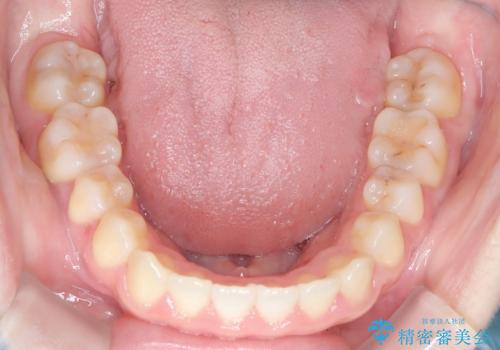

前歯のガタツキ、前歯の噛み合わせ(開咬)をインビザライン治療で治しました

- 前歯のがたつき、噛み合わせが気になるとのことで来院された患者様です。

インビザラインを使用して治療しました。

前歯がしっかり噛んでない状態(開咬)を治すために、前歯にゴムをかける必要があります。ゴムかけは患者様にご協力していただきます。